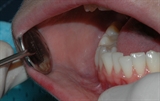

undersøkelse hos tannlegen

Tannkjøttet og tennenes benfeste blir vurdert.